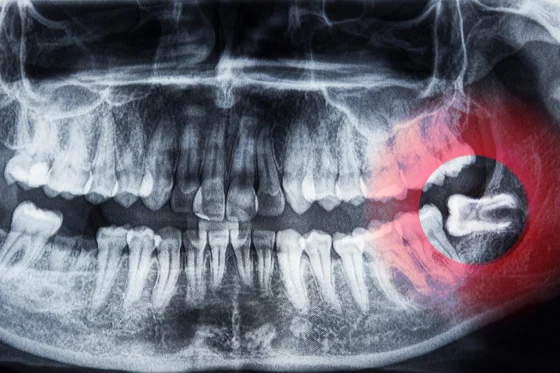

Consultation: A thorough examination and X-rays determine

the condition of your wisdom teeth.